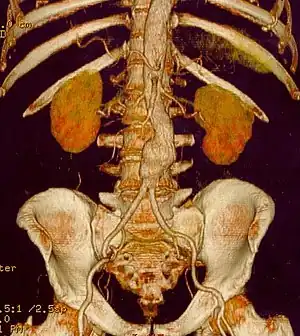

Abdominal aortic aneurysm

Abdominal aortic aneurysms (AAAs) are more common than their thoracic counterpart. One reason for this is that elastin, the principal load-bearing protein present in the wall of the aorta, is reduced in the abdominal aorta as compared to the thoracic aorta. Another is that the abdominal aorta does not possess vasa vasorum, the nutrient-supplying blood vessels within the wall of the aorta. Most AAA are true aneurysms that involve all three layers (tunica intima, tunica media and tunica adventitia). The prevalence of AAAs increases with age, with an average age of 65–70 at the time of diagnosis. AAAs have been attributed to atherosclerosis, though other factors are involved in their formation.[7]

The risk of rupture of an AAA is related to its diameter; once the aneurysm reaches about 5 cm, the yearly risk of rupture may exceed the risks of surgical repair for an average-risk patient. Rupture risk is also related to shape; so-called "fusiform" (long) aneurysms are considered less rupture-prone than "saccular" (shorter, bulbous) aneurysms, the latter having more wall tension in a particular location in the aneurysm wall.[9]

Before rupture, an AAA may present as a large, pulsatile mass above the umbilicus. A bruit may be heard from the turbulent flow in the aneurysm. Unfortunately, however, rupture may be the first hint of AAA. Once an aneurysm has ruptured, it presents with classic symptoms of abdominal pain which is severe, constant, and radiating to the back.[9]

The diagnosis of an abdominal aortic aneurysm can be confirmed by the use of ultrasound. Rupture may be indicated by the presence of free fluid in the abdomen. A contrast-enhanced abdominal CT scan is the best test to diagnose an AAA and guide treatment options.[10]